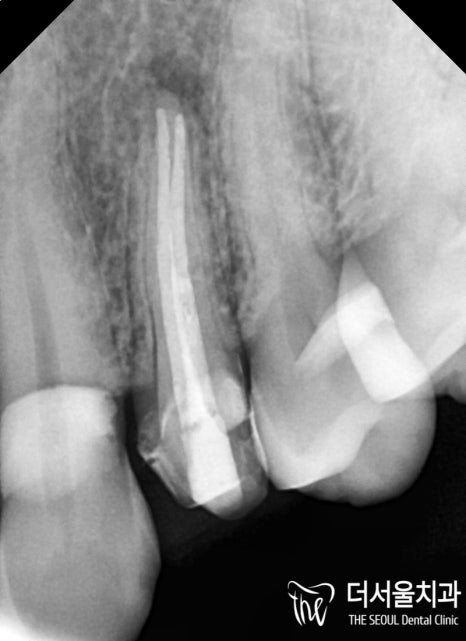

이후 밀폐 작업까지 확실하게 마친 뒤에

병소의 재발 여부를 확인하고

최종 보철을 제작하여 올려드렸는데요.

지르코니아라는 재료를 사용해서 그런지

훨씬 심미적이고 튼튼한 형태의

보철이 완성되어 올려져 있는 모습입니다^^